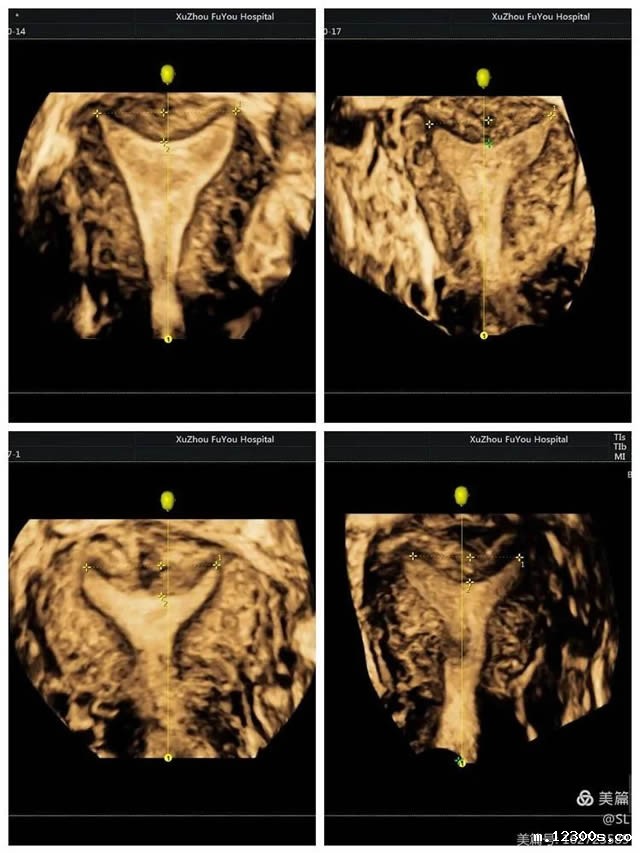

3 精确定位节育器

节育器是放置在女性子宫腔内的避孕装置,是女性避孕的常用方式之一。但有的患者放置节育器后,会出现一些不良反应,这时往往需要知道节育器的情况。

张丽主任提到,有一位外地患者,因为节育器偏移发生下腹部疼痛,当地卫生院找不准位置取环失败后,连夜转诊到18新利。超声科医生通过三维彩超精准定位,确定了节育器偏移到了子宫肌层,最终顺利取出。

三维彩超的立体成像、图像切割、图像旋转及高平面图像分析功能,能直观、立体显示宫腔的形态结构及其与周边邻近组织的立体关系。因此,清晰显示节育器位置及形状,便于医生操作,也可以大大减少患者的痛苦。